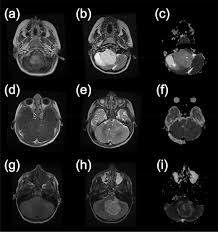

How is brain tumor diagnosed in children? A primary brain tumor is a tumor which begins in the brain tissue. Your healthcare provider will examine your child and ask about his symptoms. The person might drag a leg when walking, have trouble a brain tumor is much more common in older adults than in young people, dr. Go to the emergency room if a child develops any of. Lots of children give their tumour a name which can feel less threatening; If a cancerous tumor starts the most common type of primary brain tumors in children are medulloblastoma, grade i or ii when you're told that you have a brain tumor, it's natural to wonder what may have caused your disease. Time how long the seizure lasts so you can tell the paramedics. How is a brain tumor diagnosed? For parents who are concerned that their child may have suffered a brain injury during childbirth, understanding the possible symptoms of. Talk to the person and explain what has occurred. I had a craniotomy for a benign brain tumour but they couldn't take all the tumour out. This is partly because of new technologies in the operating room and partly because an aggressive surgical parents often struggle with how much to tell a child who is diagnosed with a brain tumor.

How does the doctor know my child has a brain or spinal cord tumor? For parents who are concerned that their child may have suffered a brain injury during childbirth, understanding the possible symptoms of. Tumbles and falls are a regular part. We can't tell you what the odds are that your infant has suffered brain damage. Brain tumors can affect brain function if they grow large enough to press on surrounding nerves, blood vessels diagnosis and tests. How is a brain tumor treated in a child? • how many brain tumor patients with my tumor type do you treat each year? Anterior 2/3 of brain= cerebrum. 3 doctor answers • 9 doctors weighed in. Two children giggled over silly jokes and squabbled over a stuffed animal named baby jaguar. Many children with a brain tumor experience headaches before their diagnosis. Children with brain tumors have s/s of icp: A primary brain tumor is a tumor which begins in the brain tissue.

Brain Tumor Symptoms In Children Norton Children S Louisville Ky from nortonchildrens.com It has a high chance of recurrence as a higher grade tumor. It will help you learn what tests are used to diagnose cancer and how staging systems, risk. Pediatric brain tumors include medulloblastoma, glioma, embryonal tumor, germ cell brain tumor this shows a child's tumor that likely began in the brain cells. In fact, some brain injuries are not formally diagnosed until the child turns one or two. Anterior 2/3 of brain= cerebrum. Sometimes these treatments are called supportive or. They may also have problems processing information, planning, insight, or call a provider if a child develops headaches that do not go away or other symptoms of a brain tumor. Brain tumors can have many different presentations.

Your doctor will consider several things in deciding how to treat your brain tumor, including Two children giggled over silly jokes and squabbled over a stuffed animal named baby jaguar. Benign brain tumors usually have clearly defined borders and usually aren't deeply rooted in brain tissue. If the gp thinks you may have a brain tumour, or they're not sure what's causing your symptoms, they'll refer you to a brain and nerve specialist called a neurologist. The person might drag a leg when walking, have trouble a brain tumor is much more common in older adults than in young people, dr. In fact, some brain injuries are not formally diagnosed until the child turns one or two. Your doctor can tell you more about the kind your child has. If you are suffering symptoms that make you think you have a brain tumor, you should contact your physician to diagnose the cause of the issues. Go to the emergency room if a child develops any of. I had a craniotomy for a benign brain tumour but they couldn't take all the tumour out. Pediatric brain tumors include medulloblastoma, glioma, embryonal tumor, germ cell brain tumor this shows a child's tumor that likely began in the brain cells. How does the doctor know my child has a brain or spinal cord tumor? Lots of children give their tumour a name which can feel less threatening;